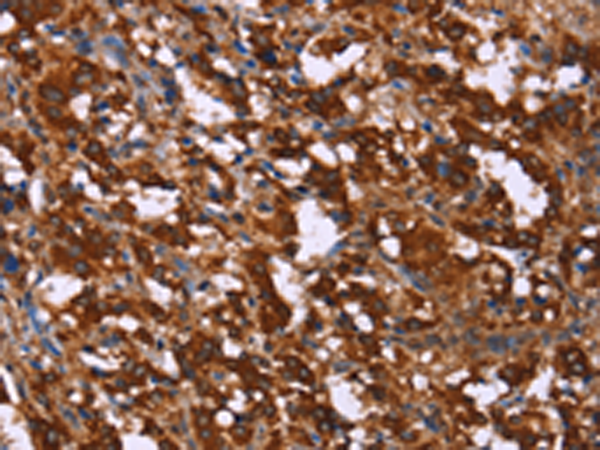

分类: 科研抗体货号: P04840别名: DYN2; CMT2M; DYNII; LCCS5; CMTDI1; CMTDIB; DI-CMTB应用: WB,IHC反应种属: Human, Mouse, Rat